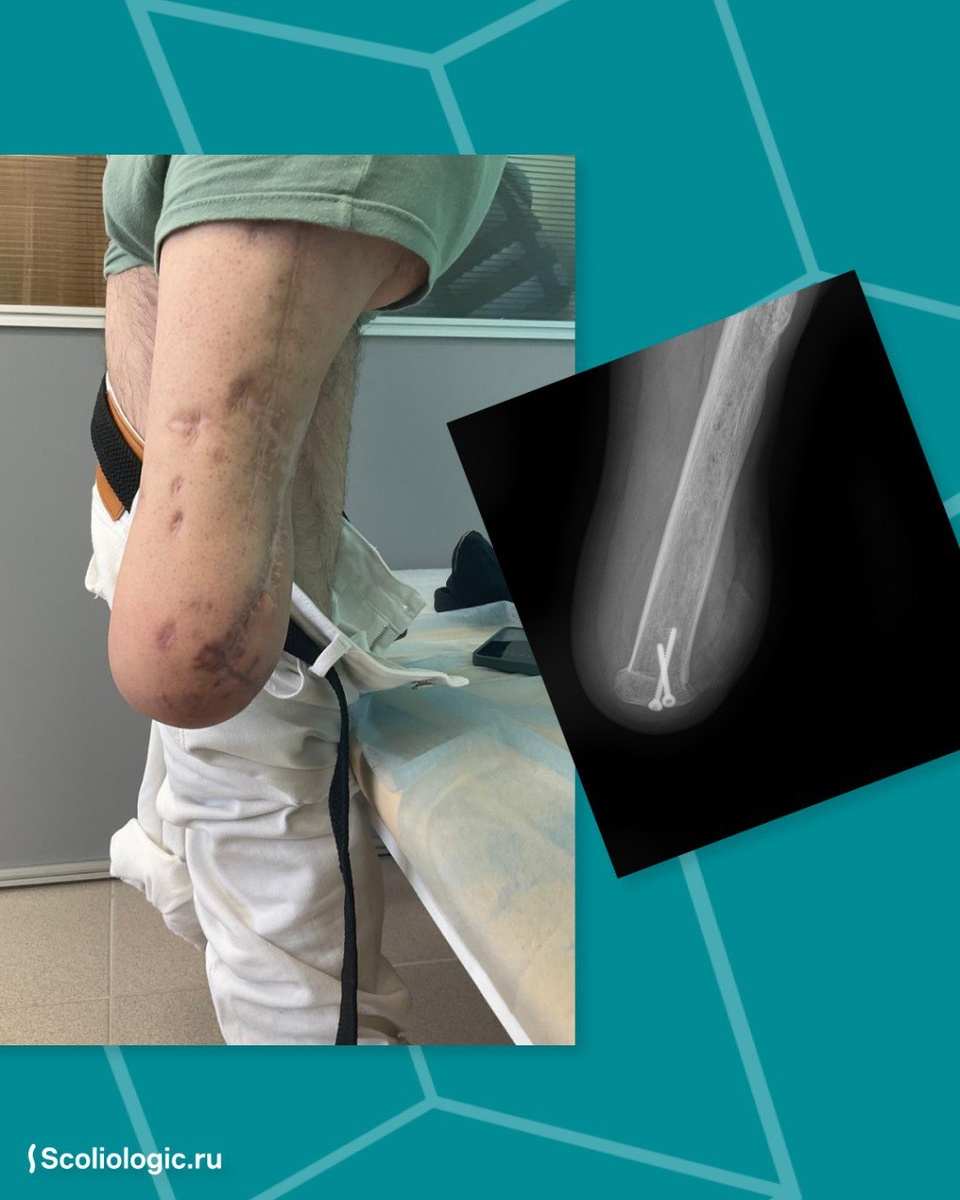

Молодой человек, 23 года, получил минно-взрывное ранение. Почти год он передвигался на костылях, так как не мог опираться на поврежденную ногу. Когда стало понятно, что ампутация неизбежна, его направили в Scoliologic.ru, чтобы определить, на каком уровне конечности ее проводить.

Пациент был убежден, что его ждет ампутация голени. Но осмотр показал, что ситуация сложнее: функции мышц задней поверхности бедра были полностью утрачены, а ягодичные мышцы значительно атрофированы.

Конечно, у пациента был выбор: оставить, всё, как есть, или попытаться что-то сделать. И он выбрал второе. И это сработало! Через месяц интенсивных тренировок с реабилитологами ему удалось улучшить функцию средней и малой ягодичных мышц. После этого было принято решение провести ампутацию по типу вычленения в коленном суставе с формированием опорной поверхности.